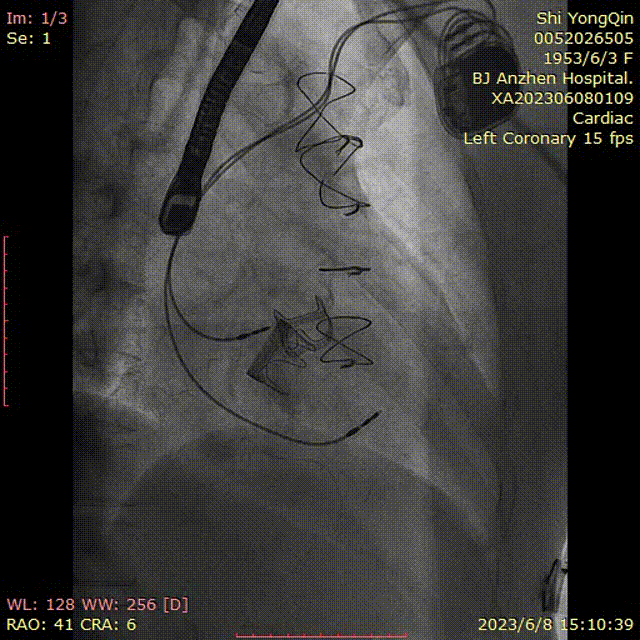

患者全麻,摆体位可寻找衰败生物瓣的切线投照体位,后消毒铺巾,穿刺双侧股静脉,左侧股静脉植入临时起搏器,右侧股静脉作为主入路,在超声指引下,按术前CT评估要求穿刺房间隔到达左心房,肝素化后(ACT>250秒),导入Agilis可调弯鞘管到达左心房,Pig造影导管跨过二尖瓣到达左心室心尖部,导入Safari导丝到达左心室;以12×40mm球囊扩张房间隔确认SAPIEN 3瓣膜可通过后,导入反向安装的23mm+3ml瓣膜到达下腔静脉,组装成功后,翻转其调弯系统后送入到左心房,跨过衰败的二尖瓣,在切线投照体位定位精确后,快速心室起搏下释放瓣膜,见瓣膜位置良好,超声显示无瓣周漏,测量左心室和桡动脉压差稍增高,超声显示LVOT流速稍增快;撤出瓣膜输送系统及导丝,撤出临时起搏电极,局部加压包扎,患者清醒后安返病房。

确认DSA投照体位